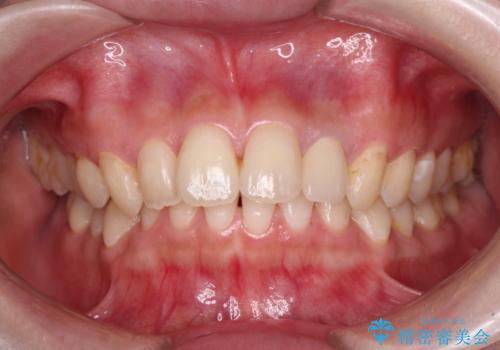

根管治療はやり直さずに、ファイバーポストを使用した土台を植立してオールセラミッククラウンにて補綴することとしました。

神経を取り除いた歯は時間とともに変色してきます。

クリーニングやホワイトニングでは改善できないため、オールセラミッククラウンなどによる補綴治療が必要となります。